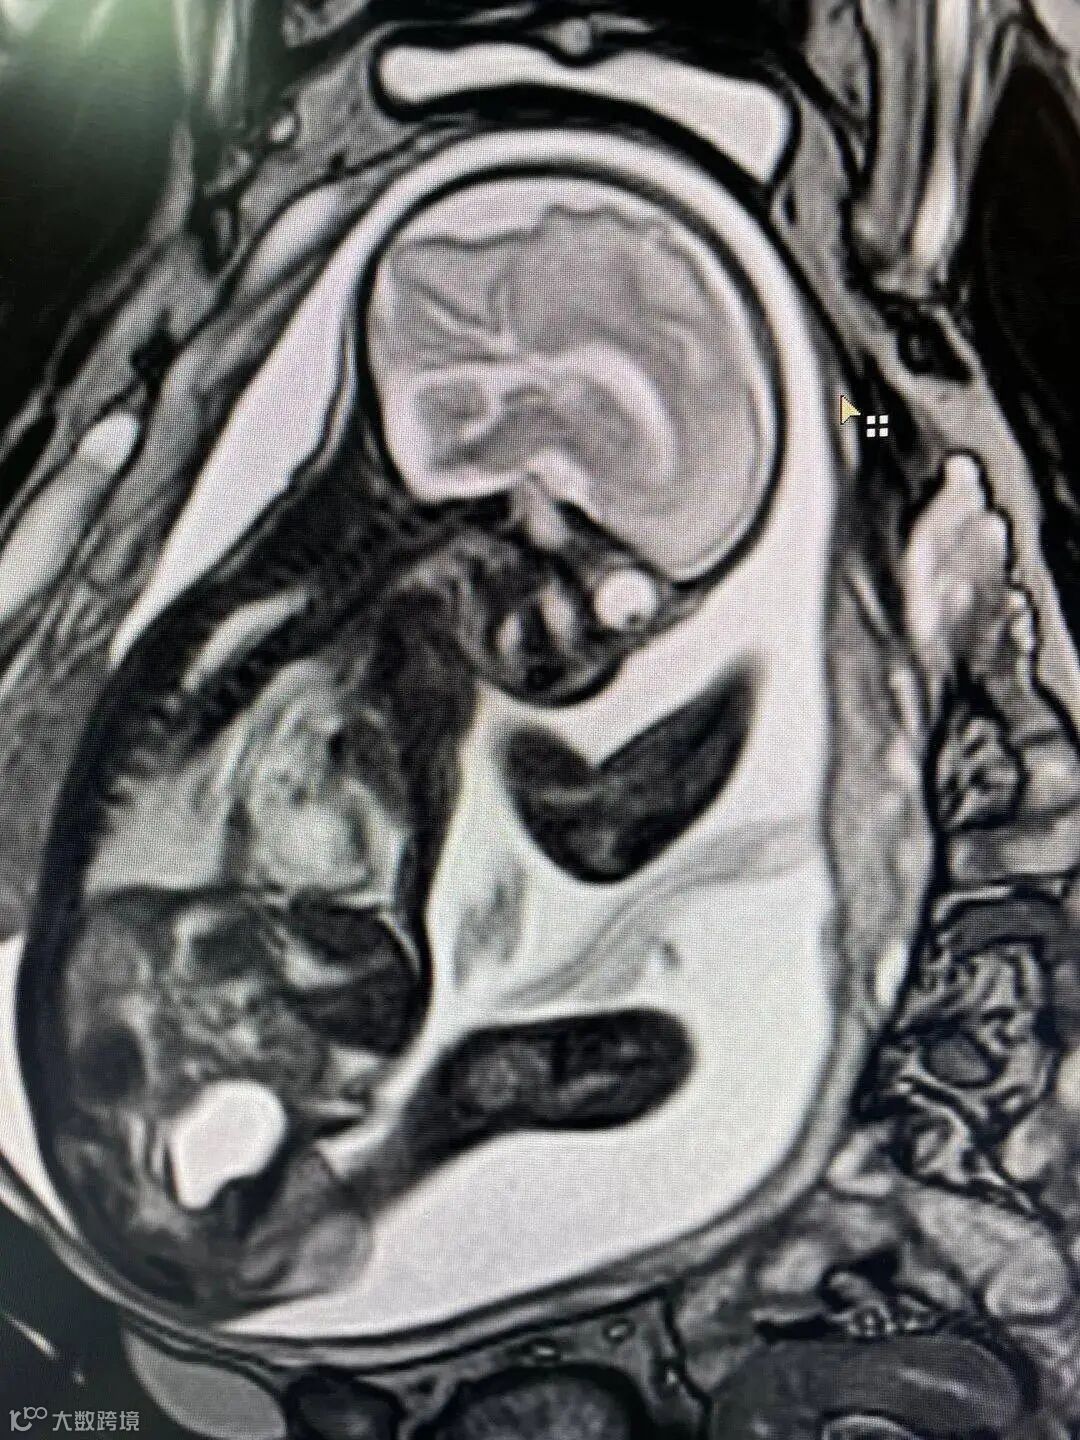

真相:磁共振没有辐射,所妊娠期MR检查相对安全,在孕妇或胎儿的获益高于潜在风险时,可以进行MR平扫检查,尤其是一些高危孕妇,利用它进行诊断很重要,如在大排畸中检查有异常的孕妇,可以联合核磁共振检查,特别是对于胎盘前置等凶险情况,磁共振可以早诊断,为治疗抢占时机做好预案。